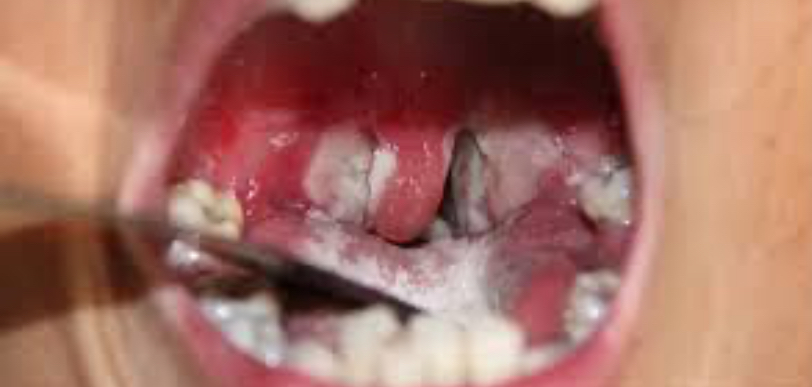

يجدر بالذكر أن بلادنا تشهد عودة لظهور مرض الدفتيريا منذ أكتوبر 2023 بمقاطعة باسكنو، كما شهد عام 2024 تسجيل عشرات الحالات منه في ولايتي الحوض الشرقي وكوركول، وفي هذا العام (2025) تم تسجيل 202 حالة إصابة من هذا المرض بولايات الحوضين ولعصابه، شُفيت منها 154 حالة، وتوفيت 15 حالة (7 في لعصابه + 8 في الحوض الغربي)، هذا في حين تخضع 41 حالة للعلاج، منها 22 في المستشفيات و19 في العلاج الخارجي.